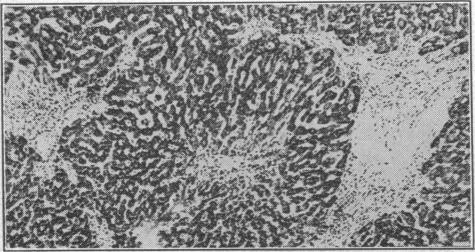

SHALDON S, SHERLOCK S

Br Med J. 1957 Sep 28;2(5047):734-8. doi: 10.1136/bmj.2.5047.734.